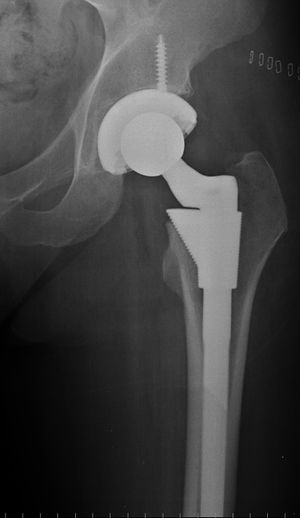

صورة بأشعة إكس، مفصل المريض (يسار الصورة) تم استبداله، with the ball of this ball-and-socket joint replaced by a metal head that is set in the thighbone or femur and the socket replaced by a white plastic cup (clear in this X-ray). Pelvic anatomy consistent with that of a female (large infrapubic angle, large pelvic opening). | |

استبدال مفصل الورك Hip replacemen، هي عملية جراحية يتم فيها استبدال مفصل الورك بمزورعة طبية صناعية. يمكن أن تجرى جراحة استبدال مفصل الورك كاستبدال تام أو نصفي. تهدف هذه الجراحة بشكل عام إلى إزالة ألم التهاب المفصل أو لإصلاح تخرب المفصل الفيزيائي كجزء من علاج كسر مفصل الورك. يتألف استبدال مفصل الورك التام (رأب مفصل الورك التام) من استبدال كل من الحق acetabulum ورأس الفخذ في حين يستبدل بشكل عام في تصنيع المفصل النصفي (رأب المفصل النصفي) رأس الفخذ فقط. تعتبر عملية استبدال مفصل الورك حالياًً عملية الجراحة العظمية الأكثر نجاحاً و موثوقيةً حيث أبدى 97% من المرضى تحسناً ملحوظاً.